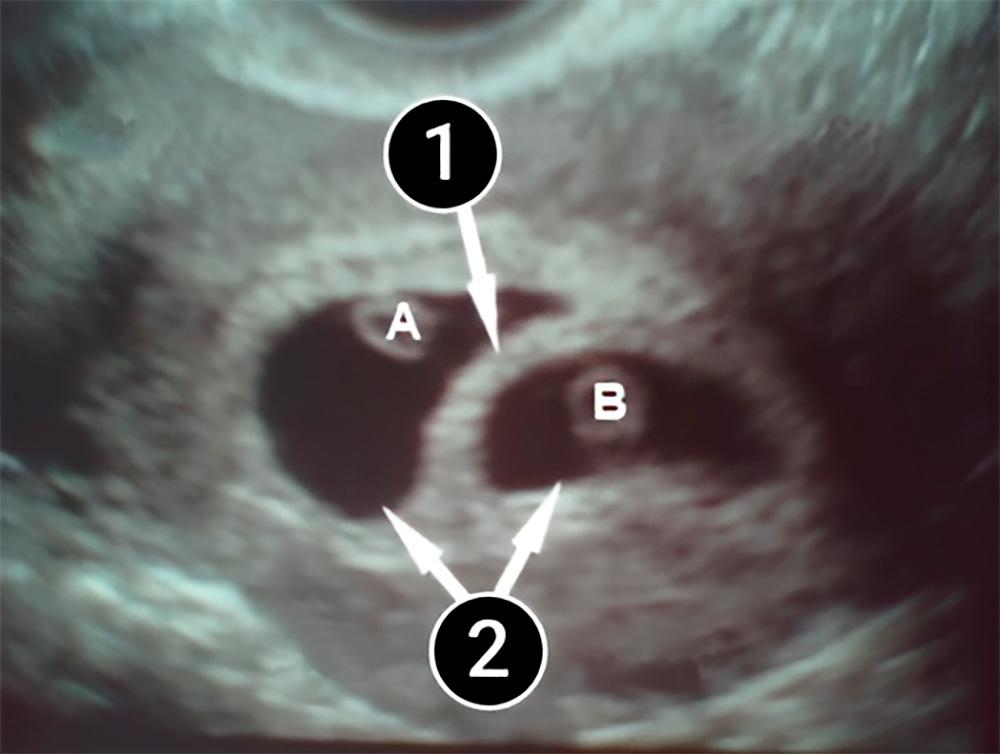

Lo que podemos ver en un ultrasonido

Esta foto muestra el desarrollo de unos gemelos. Los óvulos fetales ocupan casi la mitad del útero, se ve como un borde de luz, rodeado por una gruesa capa, que es el endometrio.

Hay una clara separación entre los dos óvulos fetales, lo que sugiere que los gemelos son heterogéneos (o fraternos) y se desarrollarán por separado.

Los embriones en sí no son visibles en la imagen, pero se pueden ver sus sacos fetales (cada uno tiene el suyo). Es a través del saco que el feto recibe proteínas, oligoelementos y aminoácidos. En la foto están marcados con las letras A y B.

A estas alturas del embarazo, el diagnóstico de "gemelos" aún no puede considerarse definitivo, ya que existe un fenómeno misterioso (pero no raro) conocido como síndrome del gemelo desaparecido. Al principio del embarazo, una mujer puede tener dos o incluso tres embriones en el útero, pero sólo se desarrolla uno y no queda rastro del segundo.